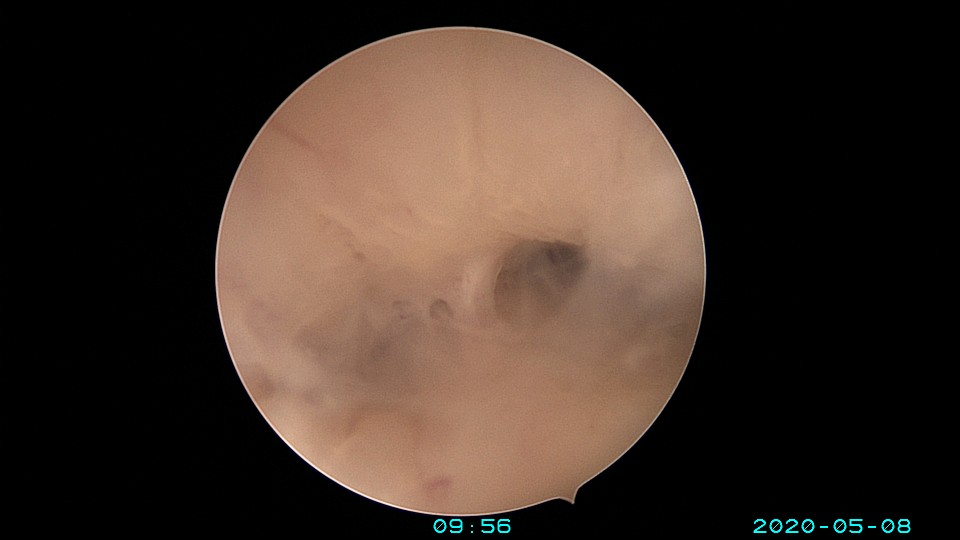

患者32岁,G10P1,剖宫产1次。2020年2月人流术后闭经2+月,2020年5月宫腔镜探查见剖宫产切口憩室,宫颈内口以上广泛封闭粘连,AFS评10分,双极电针分粘效果差,扩张宫颈管,改用双极电切分粘,恢复宫腔形态,显露双侧输卵管开口。2020年6月宫腔镜二探取球囊,宫腔形态正常,双侧输卵管开口可见。2020年10月自然妊娠,2021年2月初的某一天,在电梯里,病人的老公认出我是给他老婆做手术的医生,表达感谢之余,讲病人因先兆流产在产科保胎,情绪不稳定,甚至想终止妊娠,医生及家属努力安抚病人。2021年5月,36+3周剖宫产分娩。现37岁,G11P2。